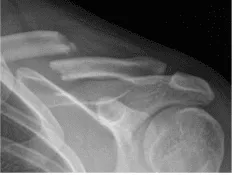

Se presentó una XR en la consulta y se encontró fractura clavicular en el centro del diástico con 1 cm de sobreposición y desplazamiento moderado. Las fracturas de la clavícula en la diáfise media son lesiones traumáticas frecuentes producidas por un impacto directo en la cintura escapular, y son más comunes en adultos jóvenes y activos.

Clavícula izquierda en posición axial